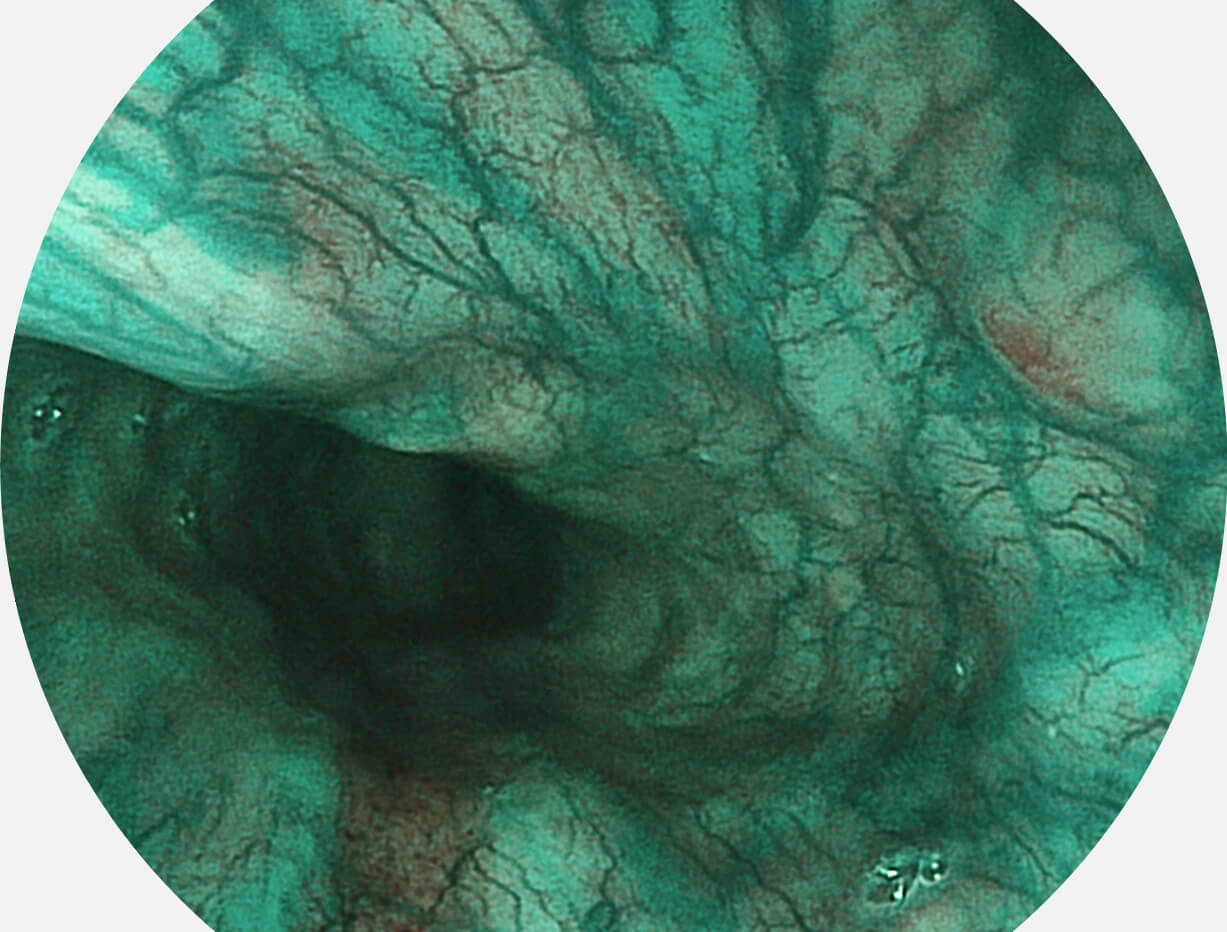

强调浅层黏膜结构的同时,保证照明亮度和提升浅层微血管与中层血管颜色对比度,病变边界更清晰。

白光图像

VIST图像